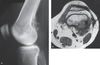

Parosteal Osteosarcoma.

A: A lateral radiograph of the knee shows a bony lesion emanating from the posterior cortex of the distal femur with a large, calcified soft tissue mass. Note that the densest calcification is central and the periphery is only faintly calcified, characteristics that are typical for a parosteal osteosarcoma.

B: A CT through the lesion reveals the tumor to be invading the

medullary portion of the bone. This is a poor prognostic sign and is an essential information to the surgeon.

Parosteal Osteosarcoma.

A: A lateral radiograph in a different patient with a parosteal osteosarcoma shows soft tissue calcification extending from the posterior femur.

B: A proton- density axial image reveals considerable bony involvement.